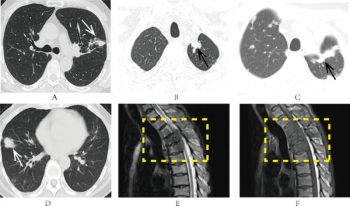

A predictive model for non-small cell lung cancer (NSCLC) recurrence, based on clinical parameters and CT findings, demonstrated an 85.2 percent AUC and 83.3 percent sensitivity rate, according to external validation testing in a new study.